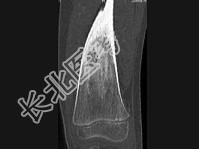

- 单项选择题男,30岁, 左大腿疼痛1年余,夜间或休息加重, 口服止痛药可缓解,结合图像, 最可能的诊断是 ( )

B、骨样骨瘤